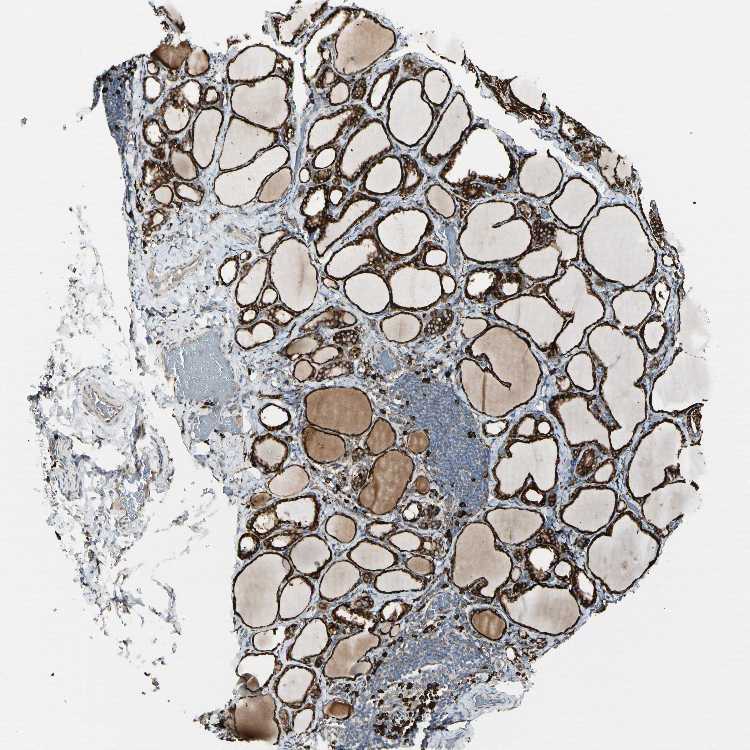

TISSUE PRIMARY DATA THYROID GLAND Show tissue menu

THYROID GLAND - Antibody stainingi

Antibody staining in the annotated cell types in the current human tissue is reported as not detected, low, medium, or high, based on conventional immunohistochemistry profiling in selected tissues. This score is based on the combination of the staining intensity and fraction of stained cells.

Each image is clickable and will lead to virtual microscopy that enables deeper exploration of all samples and also displays staining intensity scores, fraction scores and subcellular localization as well as patient and tissue information for each sample.

Antibody HPA003901Antibody HPA008424Antibody CAB005224

Glandular cells HighHighHigh